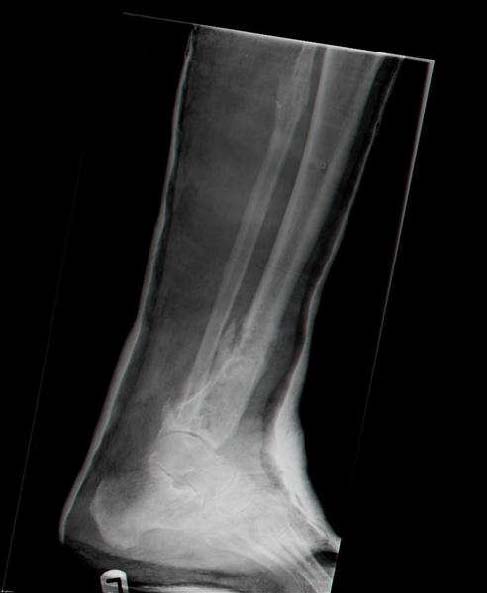

Male 54 years old, diabetic, blind in both eyes, with infected (MRSA) non union distal tibia after fracture 8 month ago. In acute phase treated by ORIF with LCP tibia and fibula. Treatment complicated by infection and after 6 month hardware was removed and treatment continued by cast fixation. You can see malposition of fragments In this stage beginning treated by Ilizarov fixation with use Hexapod system, allows anatomical position of fragments and you see signs of union.